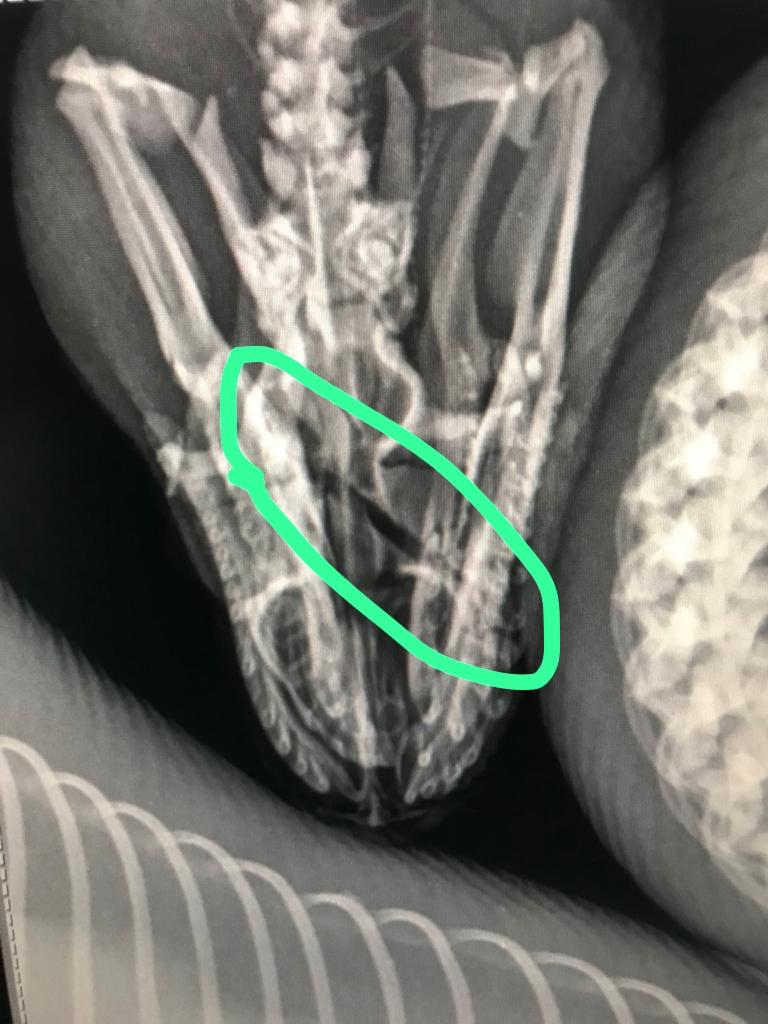

A través de rayos X se confirmaron las fracturas en el cráneo que comprometen un globo ocular que internamente está muy expuesto a la lesión.